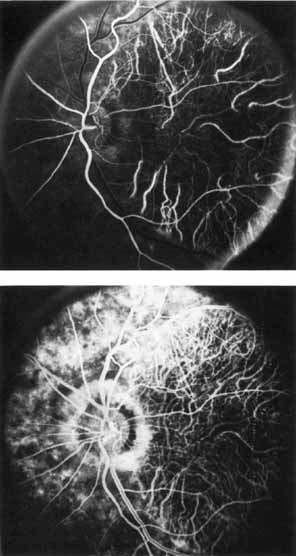

Fluorescein angiography demonstrates increased transmission of choroidal fluorescence in the macula during early phases of the study, without late leakage of dye or fluorescein staining. In addition, an annular pattern of hyperfluorescence is often seen in the macula, highlighting the bull's-eye pattern seen on fundus examination (Fig. 4). Visual field defects include central scotoma, peripheral field loss, and ring scotoma.